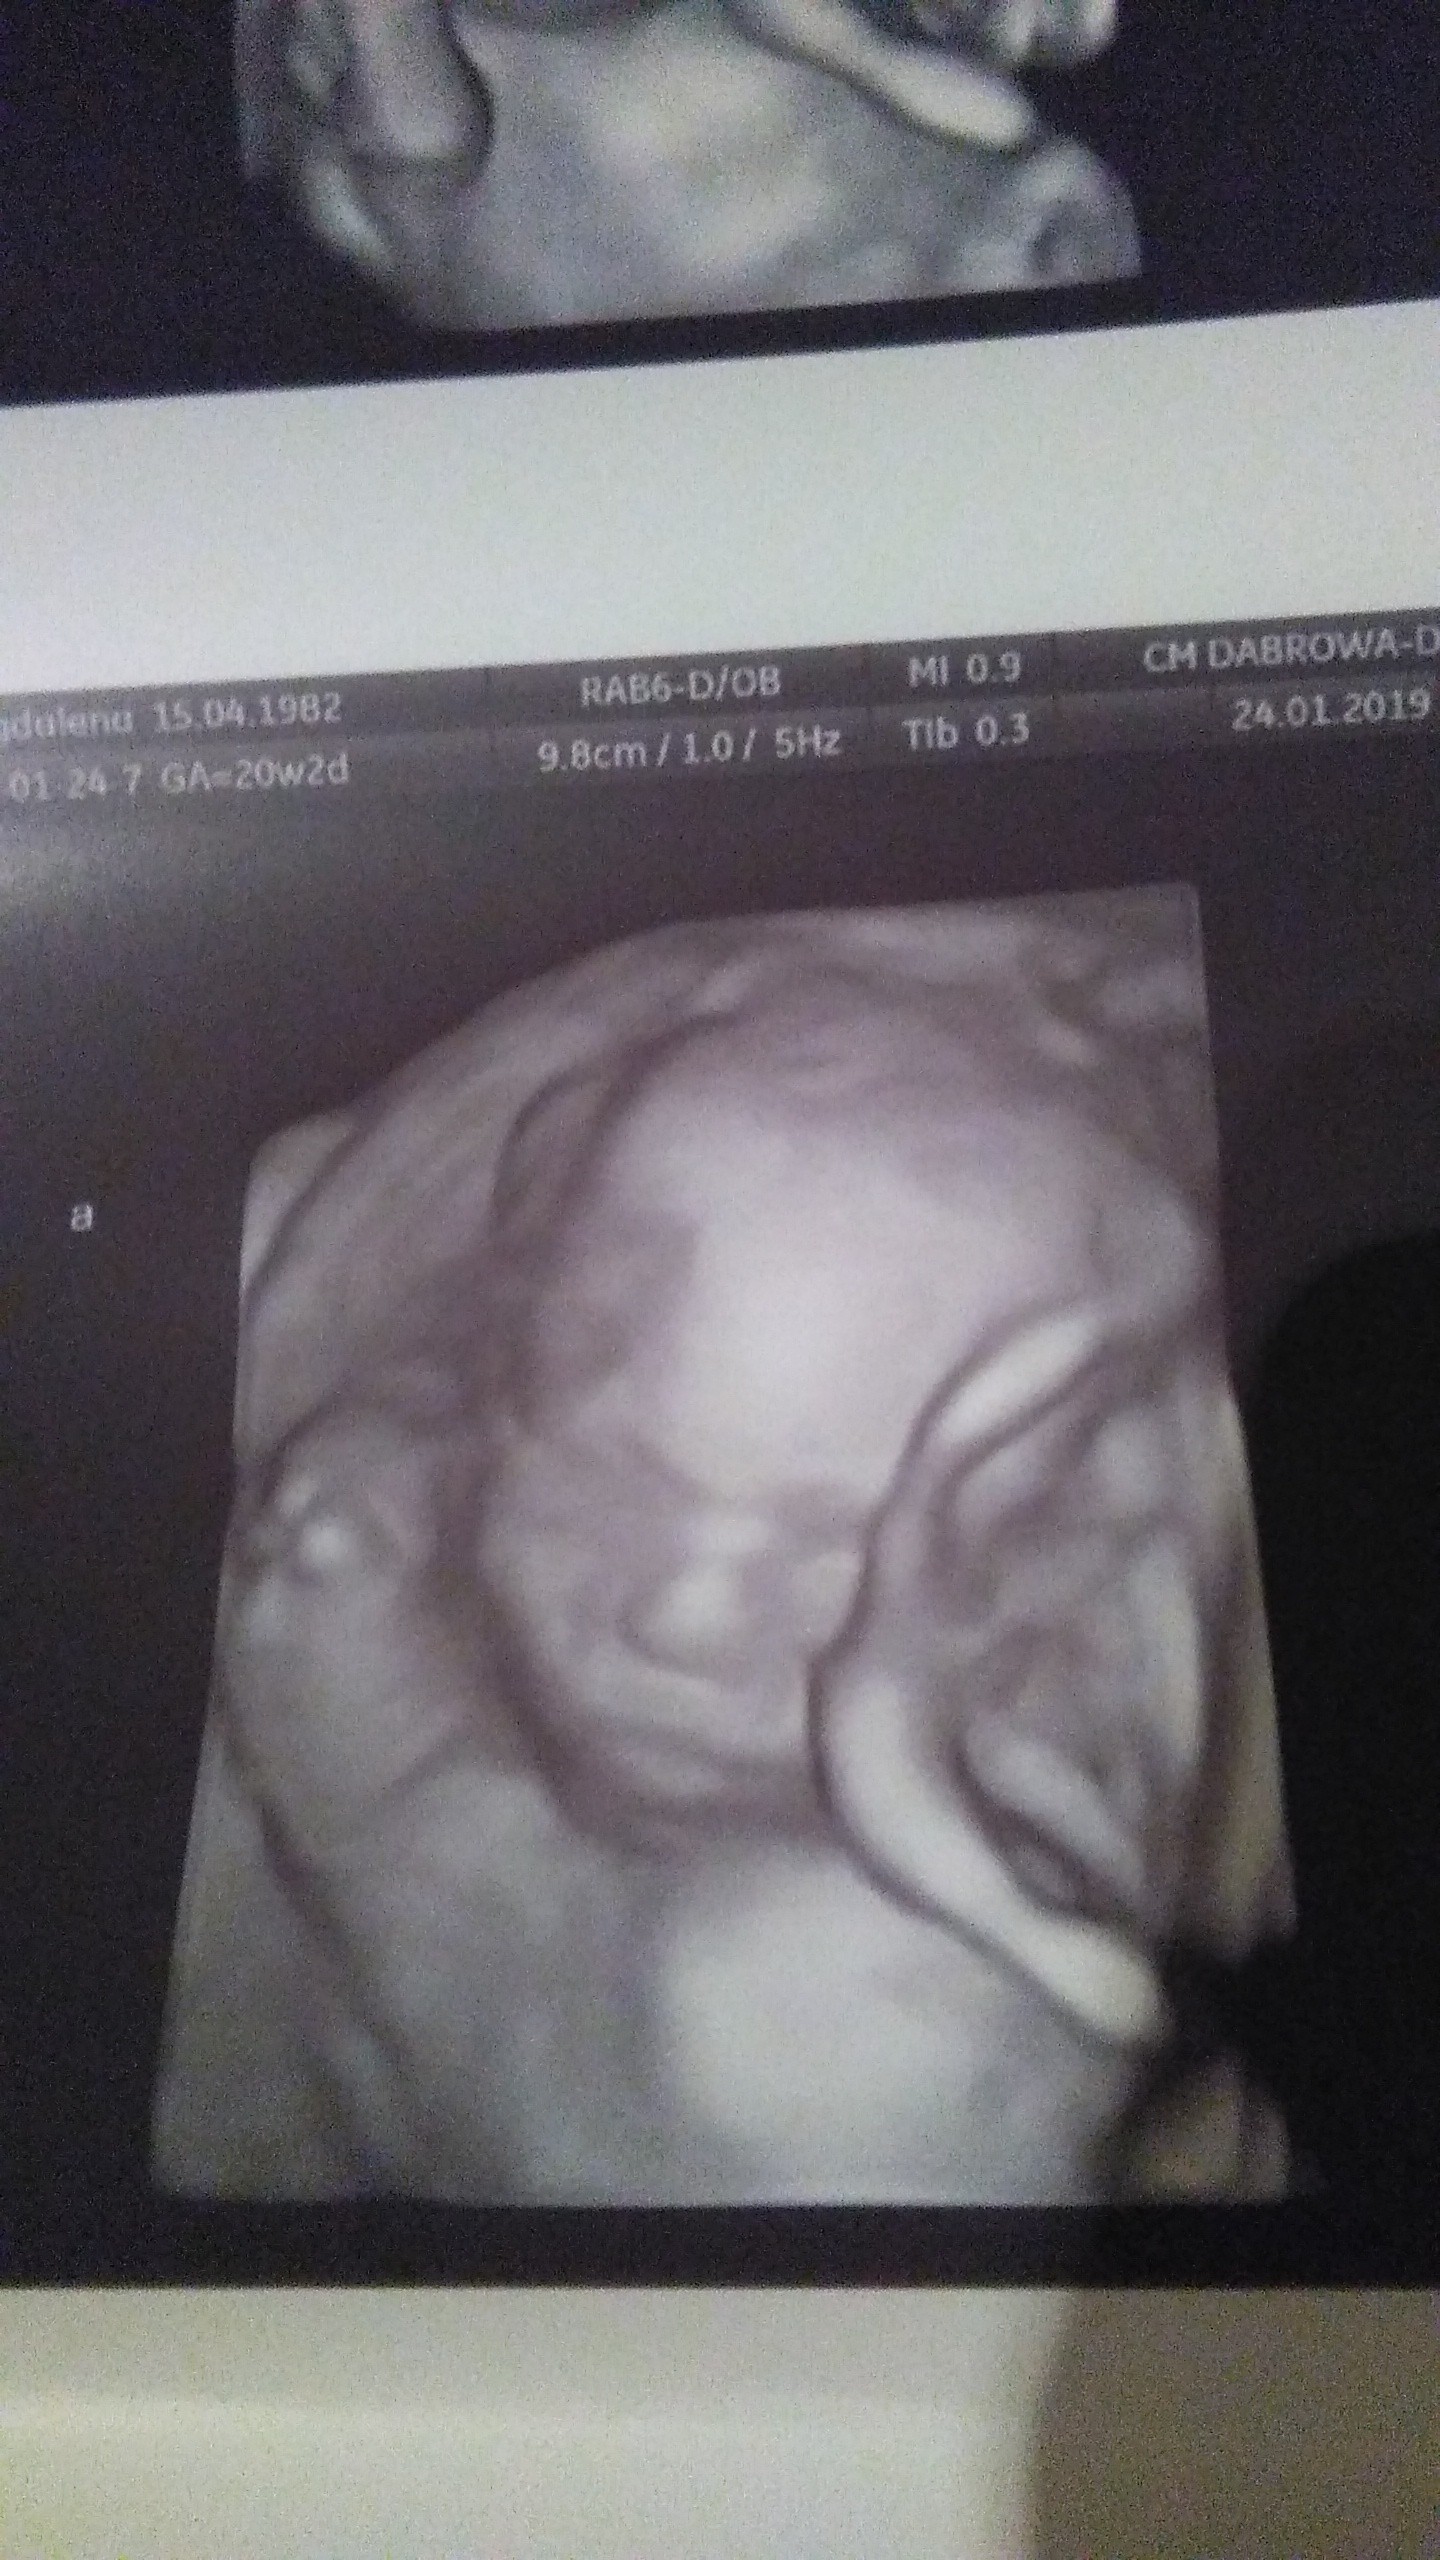

Dziewczyny walczcie dzielnie o swoje marzenia. Jako przykład przedstawiam wam mój mały wielki cud - bliźnięta jednojajowe. 20 tydzień. Trzeci transfer, podana najslabsza blastusia, która w dodatku podzieliła się i oto mamy - Olę i Izę

gratulacje oby więcej takich wiadomośći Marzenia sie spełniająDziewczyny walczcie dzielnie o swoje marzenia. Jako przykład przedstawiam wam mój mały wielki cud - bliźnięta jednojajowe. 20 tydzień. Trzeci transfer, podana najslabsza blastusia, która w dodatku podzieliła się i oto mamy - Olę i Izę